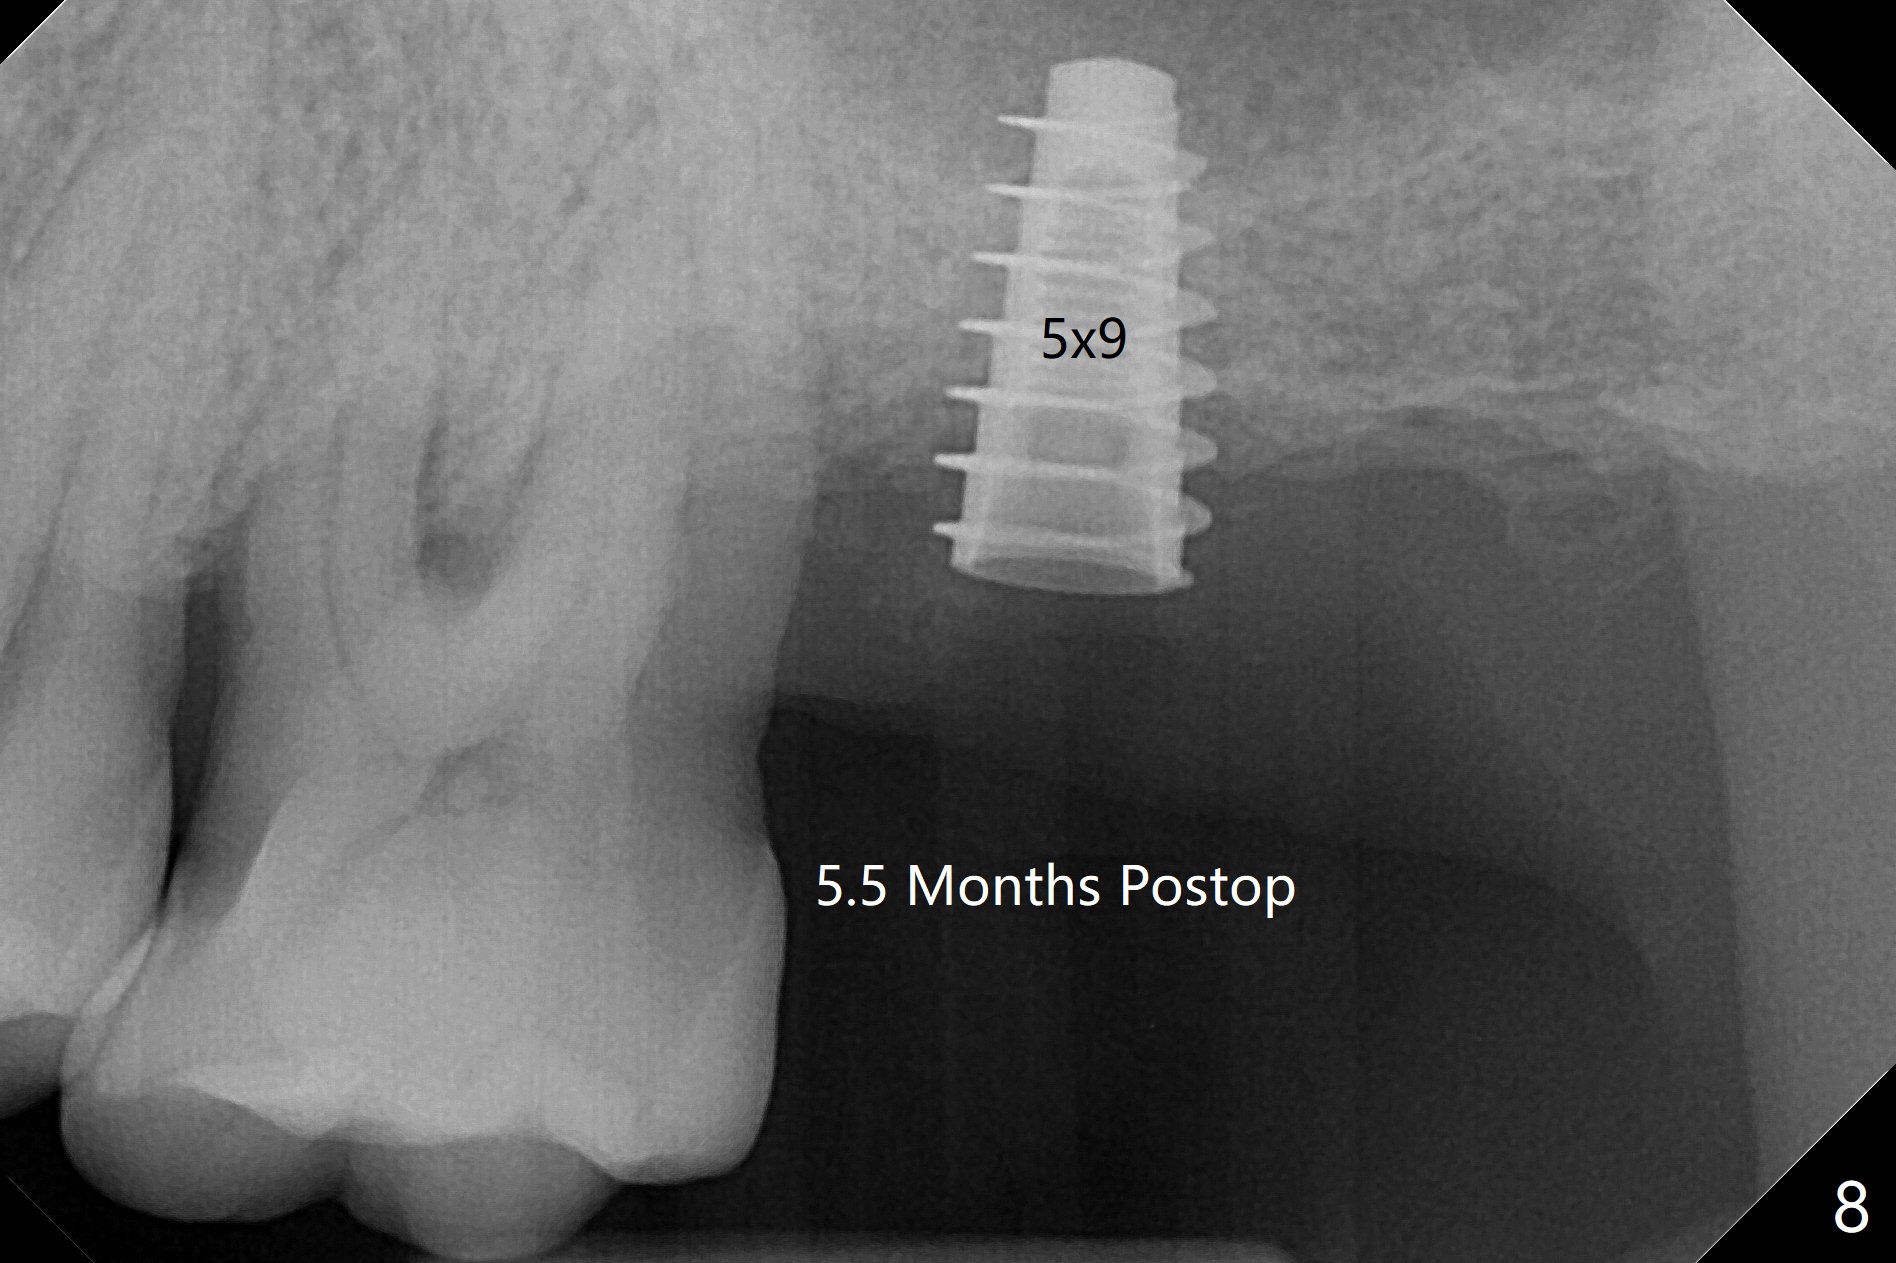

Bone在上颌窦里凝固了。其实左侧上颌窦粘膜术前增厚(图四,五:L),人工骨仿佛弥撒在上颌窦膜中(图六)。术后一周病人没有任何鼻窦症状。术后4.5月旋转愈合基台时,病人感到疼痛,终止取模(图七),两个月后复诊,做progressive loading。术后5.5月旋转愈合基台时,植体一起出来,但是上颌窦膜没有破,放置大一号植体(报废)扭力不够(图八),再大一号扭力可以(图九),放置愈合帽。由于邻牙长(图九:双箭头),牙周敷料逗留三周不掉(图十:P)。撤除后,伤口愈合正常。The

implant is stable upon uncover 3.5 months postop (Fig.11).